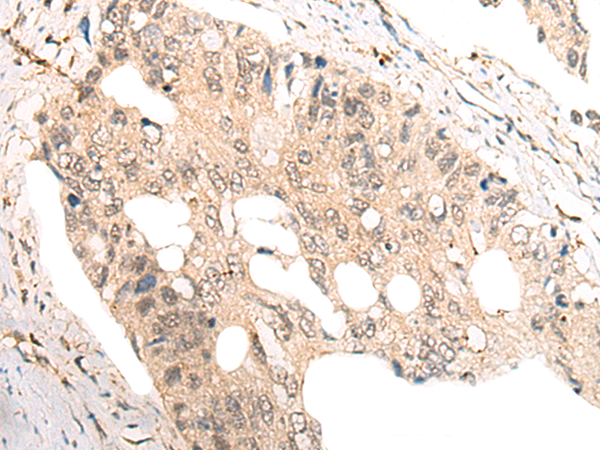

The image is immunohistochemistry of paraffin-embedded Human lung cancer tissue using 46969(COMMD1 Antibody) at dilution 1/35. (Original magnification: ?00)